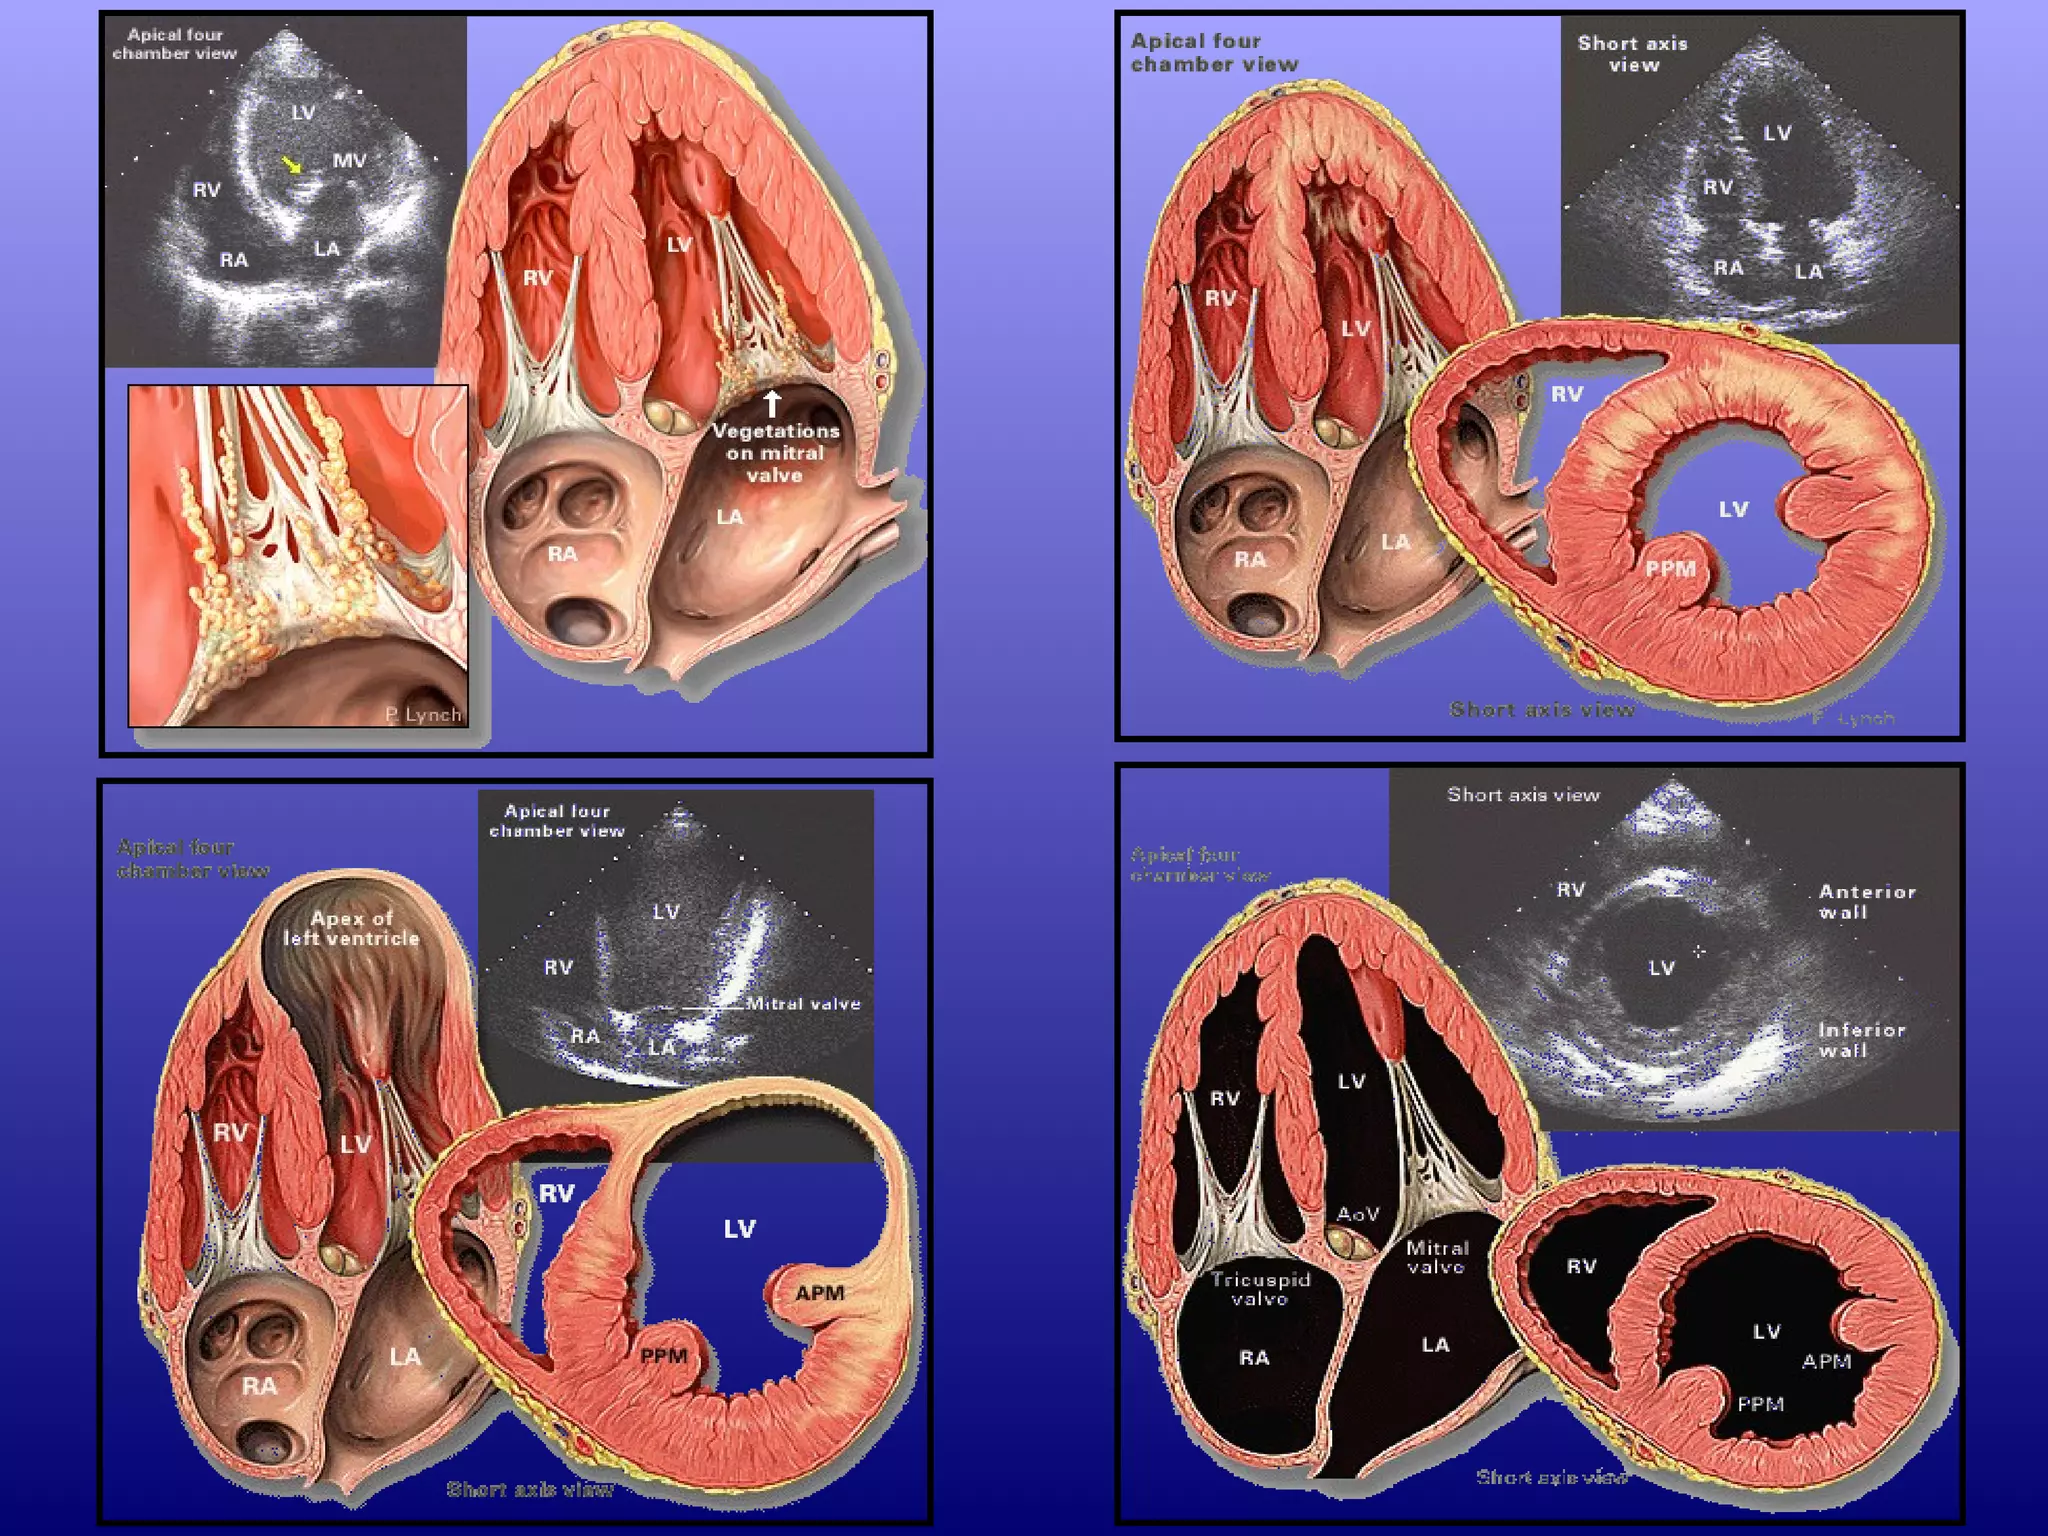

In the apical four-chamber view, all four

chambers of the heart may be seen The left

ventricle appears as a truncated ellipse,RV

triangular with the interventricular septum, apex

formed by LV, and lateral walls visualized.

With the patientmaintained in the left lateral decubitus position, the transducer is placed near the apex of the heart with an inferior orientation In the apical four-chamber view, all four chambers of the heart may be seen The left ventricle appears as a truncated ellipse,RV triangular with the interventricular septum, apex formed by LV, and lateral walls visualized. Apical four-chamber